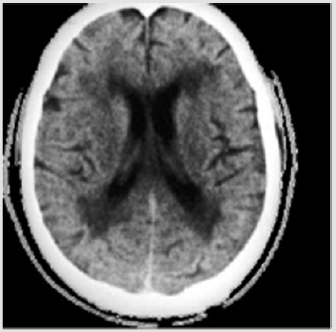

Figure 1: CT scan of the patient’s simple skull 1. Subcortical cortical atrophy and presence of leukoatrophy with dilation of the ventricular system in relation to subcortical ischemia.

The neurological examination presents discrete space-time disorientation, with Mini mental test 14 points. Presence of discinence in both hands. Light echolalia. CT scan of the skull with the presence of subcortical cortical atrophy, with increased volume of lateral ventricles due to leukoatrophy (Figure 1). Based on the clinical and tomographic findings, the patient was diagnosed with moderate mild Dementia secondary to cerebrovascular disease subcortical ischemia. After receiving information and consent from the patient, 40 rTMS sessions were applied, using the Dementia and Vascular Brain Disease protocol using the Actipulse equipment, developed in Mexico.